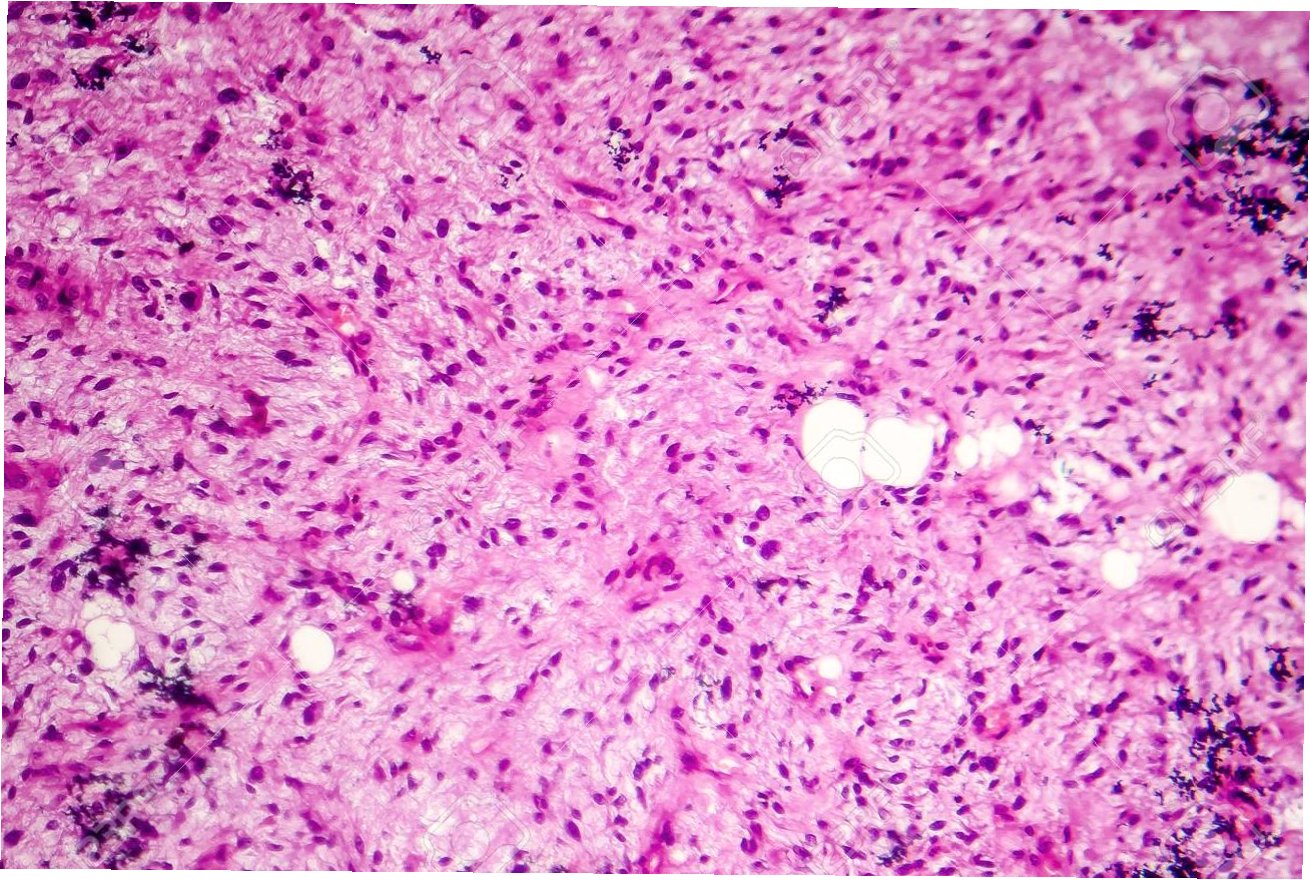

육종의 진단은 신체 검사, 영상 검사, 조직 검사 등을 통해 이루어집니다. 신체 검사에서는 종괴의 크기, 위치, 통증 유무 등을 확인하며, 영상 검사로는 X-ray, CT, MRI, 초음파 등이 사용됩니다. 특히 MRI는 연조직 육종의 정확한 진단에 매우 유용하며, CT는 전이 여부를 확인하는 데 사용됩니다. 조직 검사는 육종을 확진하는 가장 중요한 방법으로, 종괴의 일부를 채취하여 현미경으로 관찰하여 육종의 종류를 판별합니다. 조직 검사 결과는 치료 계획 수립에 결정적인 역할을 합니다. 정확한 진단을 위해서는 숙련된 의료진의 판단과 전문적인 검사 시스템이 필수적입니다.